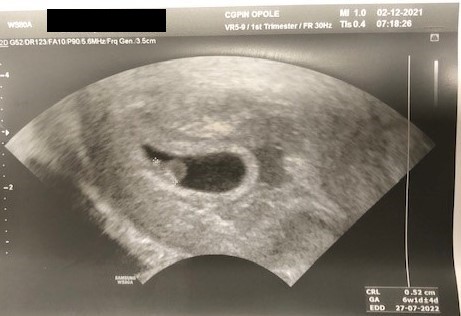

no ja juz po wizycie :) 6+1, zarodek 5,2 mm

bede musiala brac luteine i Acard

narazie wsio OK ufff :D

• 1.jpg

1.jpg

32 KB · Wyświetleń: 86